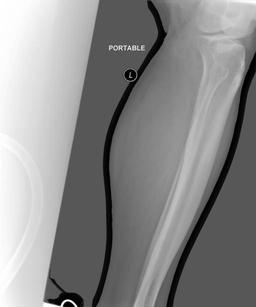

A.4 Data curation of imaging datasets

Large datasets often contain instances that are mislabelled or out of distribution [35]. We used BioViL-T to perform pairwise ranking of instances in MIMIC-CXR (Section 3.3, ) and selected representative examples found in the dataset. Our method is able to select the most appropriate image for a range of different image-acquisition or image-processing issues (Figure A.7).

We found that many lateral acquisitions in the dataset were unexpectedly labelled as frontal (Figure 7(a)). Some images contained only noise (Figure 7(b)), non-human samples (Figures 7(d) and 7(e)) or incorrect anatomy (Figure 7(g)). Often, acquisitions with an incomplete field of view (FOV) (i.e., the lungs are not completely visible) were repeated (Figure 7(c)). Lastly, post-processed images were detected by the algorithm such as contrast-enhanced scans (Figure 7(i)) that are not often used for diagnostic purposes in clinical practice.